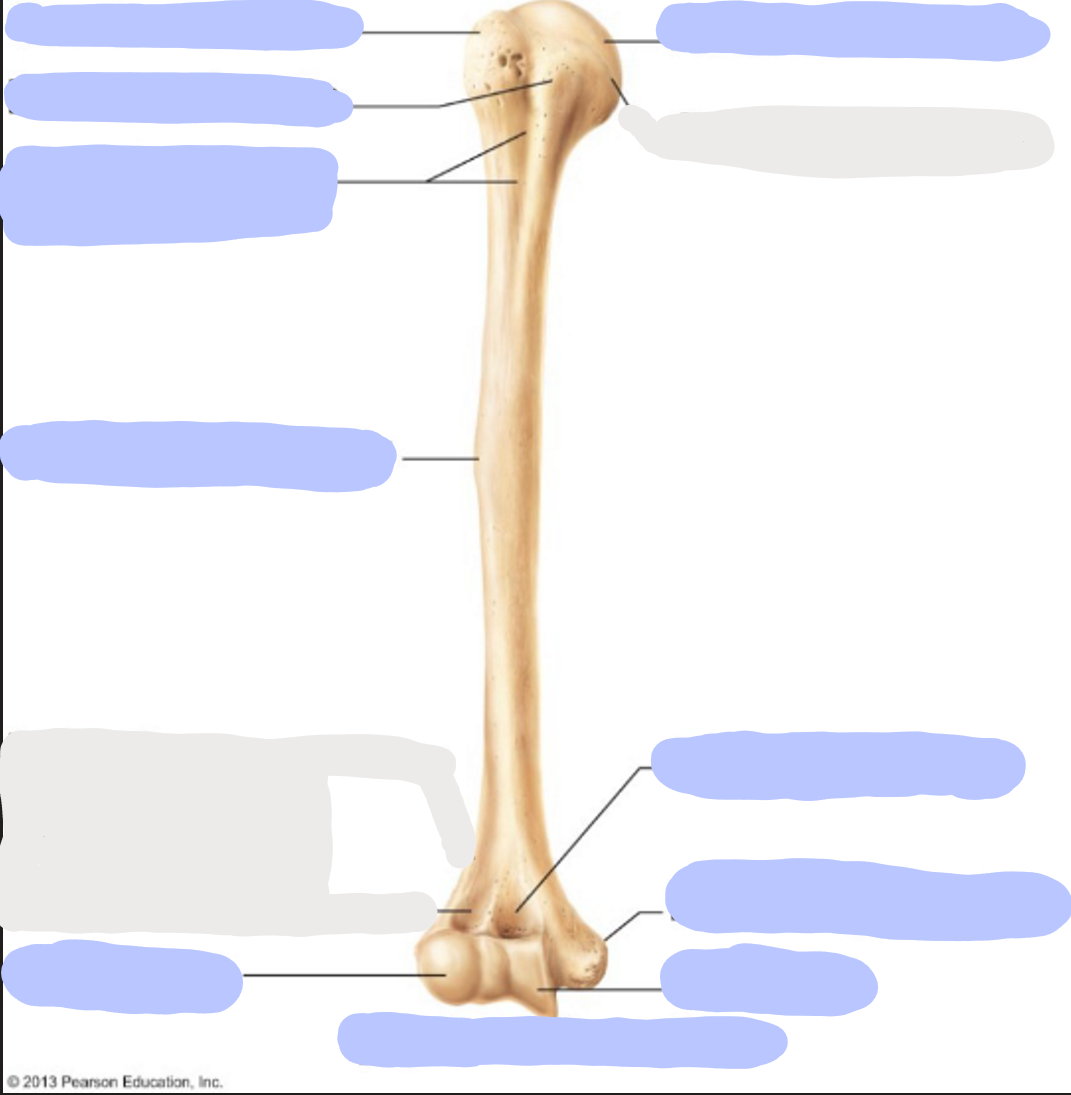

What is this picture of?

Posterior view of the Right Femur

What is here?

Where is the Head of the Femur?

What is here?

Where is the Lesser Trochanter of the Femur?

What is here?

Where is the Linea Aspera of the Femur?

What is here?

Where is the Medial Condyle of the Femur?

What is here?

Where is the Medial Epicondyle of the Femur?

What is here?

Where is the Greater Trochanter of the Femur?

What is here?

Where is the Lateral Condyle of the Femur?

What is here?

Where is the Lateral Epicondyle of the Femur?